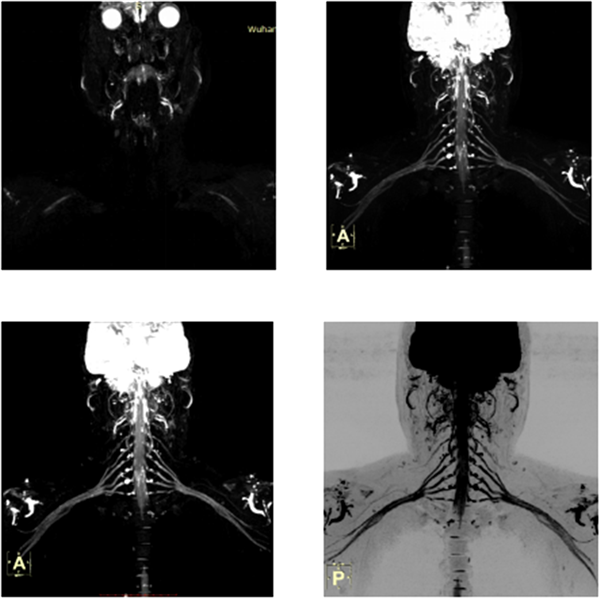

(七)类PET成像技术:光梭1.5T磁共振具有全身弥散成像(类PET成像技术)的特有功能,同时可获得与PET/CT类似临床价值,能明显降低低患者行PET/CT的经济负担,对早期恶性肿瘤检查、转移灶筛查、淋巴结转移筛查、寻找原发灶、术后放化疗后的疗效观察有较大的科研和临床价值。

臂丛神经成像